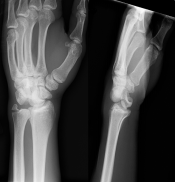

What’s the Diagnosis? Gepost op 4 januari 20184 januari 2018 door netwerkvsseh What’s the Diagnosis? @emdaily.cooperhealth.org Dit delen: Delen op X (Opent in een nieuw venster) X Share op Facebook (Opent in een nieuw venster) Facebook Delen op LinkedIn (Opent in een nieuw venster) LinkedIn E-mail een link naar een vriend (Opent in een nieuw venster) E-mail Afdrukken (Opent in een nieuw venster) Print Vind-ik-leuk Aan het laden... Gerelateerd